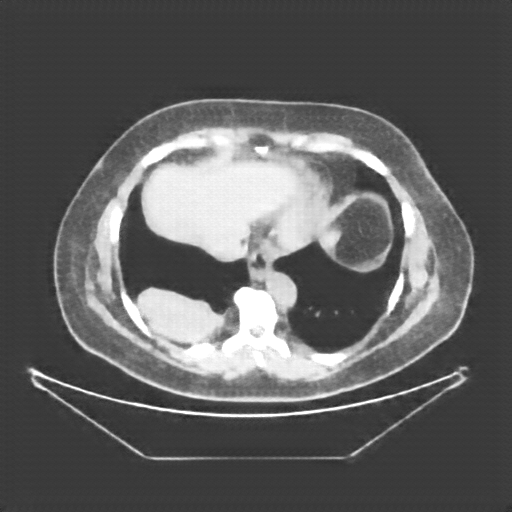

Image Grid

4×3 grid: Rows show different image types (Original NATIVE, Reconstructed NATIVE, Original VENOUS, Generated VENOUS), Columns show windowing techniques (No Window, Lung Window, Mediastinum Window)

Original NATIVE CT scan (input)

No window - Raw intensity values

Original VENOUS CT scan

No window - Raw intensity values

Original VENOUS CT scan

Lung window (WL -600, WW 1500 → Low −1350, High +150)

Original VENOUS CT scan

Mediastinum window (WL 40, WW 400 → Low −160, High +240)

Generated VENOUS CT scan (A→B translation)

No window - Raw intensity values

Generated VENOUS CT scan (A→B translation)

Lung window (WL -600, WW 1500 → Low −1350, High +150)

Generated VENOUS CT scan (A→B translation)

Mediastinum window (WL 40, WW 400 → Low −160, High +240)